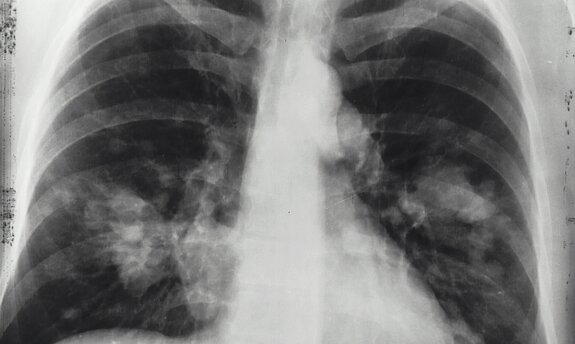

- Lungenkrebs (Thorakale Onkologie)

- Lungenhochdruck (Pulmonale Hypertonie)

- Vernarbungen der Lunge (Interstitielle Lungenerkrankungen)

- Chronisch obstruktive Lungenerkrankung (COPD)

- Asthma bronchiale

- Seltene Lungenerkrankungen